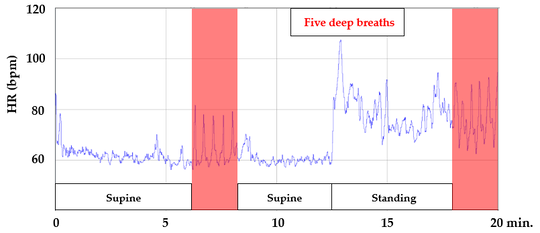

Mind-Body Connection Test

この患者のMind-Body Connection Test

X線画像に異状がなく関節の可動域が正常でない場合は、軟部組織の機能不全が起きていると考えられます。しかし、MBCTにより、心臓交感神経の過緊張が認められるため、心臓副交感神経の機能亢進、心臓交感神経の機能抑制を視野に入れての施術が必要である。また、デスクワークと聞き、パソコン画面の場所など、仕事環境の問診から、日常生活の聞き取りから改善の手法をお伝えしている。